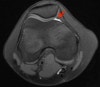

MRI의 axial view에서 transverse thick line이 보이면 medial parapatellar plica입니다.

MRI : 활막 추벽 증후군(Synovial plica syndrome)